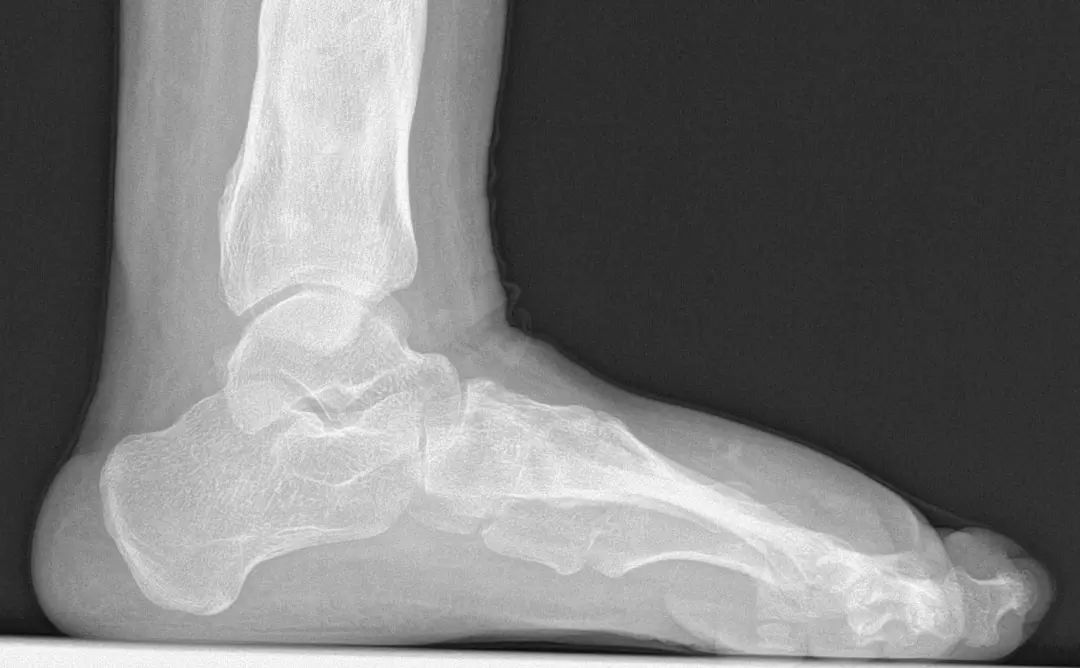

图:术前“我是慕着同济足踝外科的名而来的,”小王一边细数着脚上的疤痕一边笑着说道,“我在7岁时就做了第一次手术了,跑遍了国内知名的医院,做了三次大手术,前前后后也花了30万左右。”即使是这般残酷的现实也无法遮掩住这个女孩的乐观的笑容。

图:术前扁平足